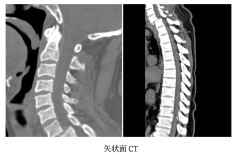

锁骨与胸骨之后:一场在“透视盲区”完成的脊柱复位战

湘雅三医院疼痛科运用“黑科技”为八旬老人解除顽固剧痛